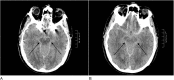

(A and B) CT brain with axial view demonstrating hyperdense gadolinium contrast in the basal cisterns extending into the Sylvian fissure